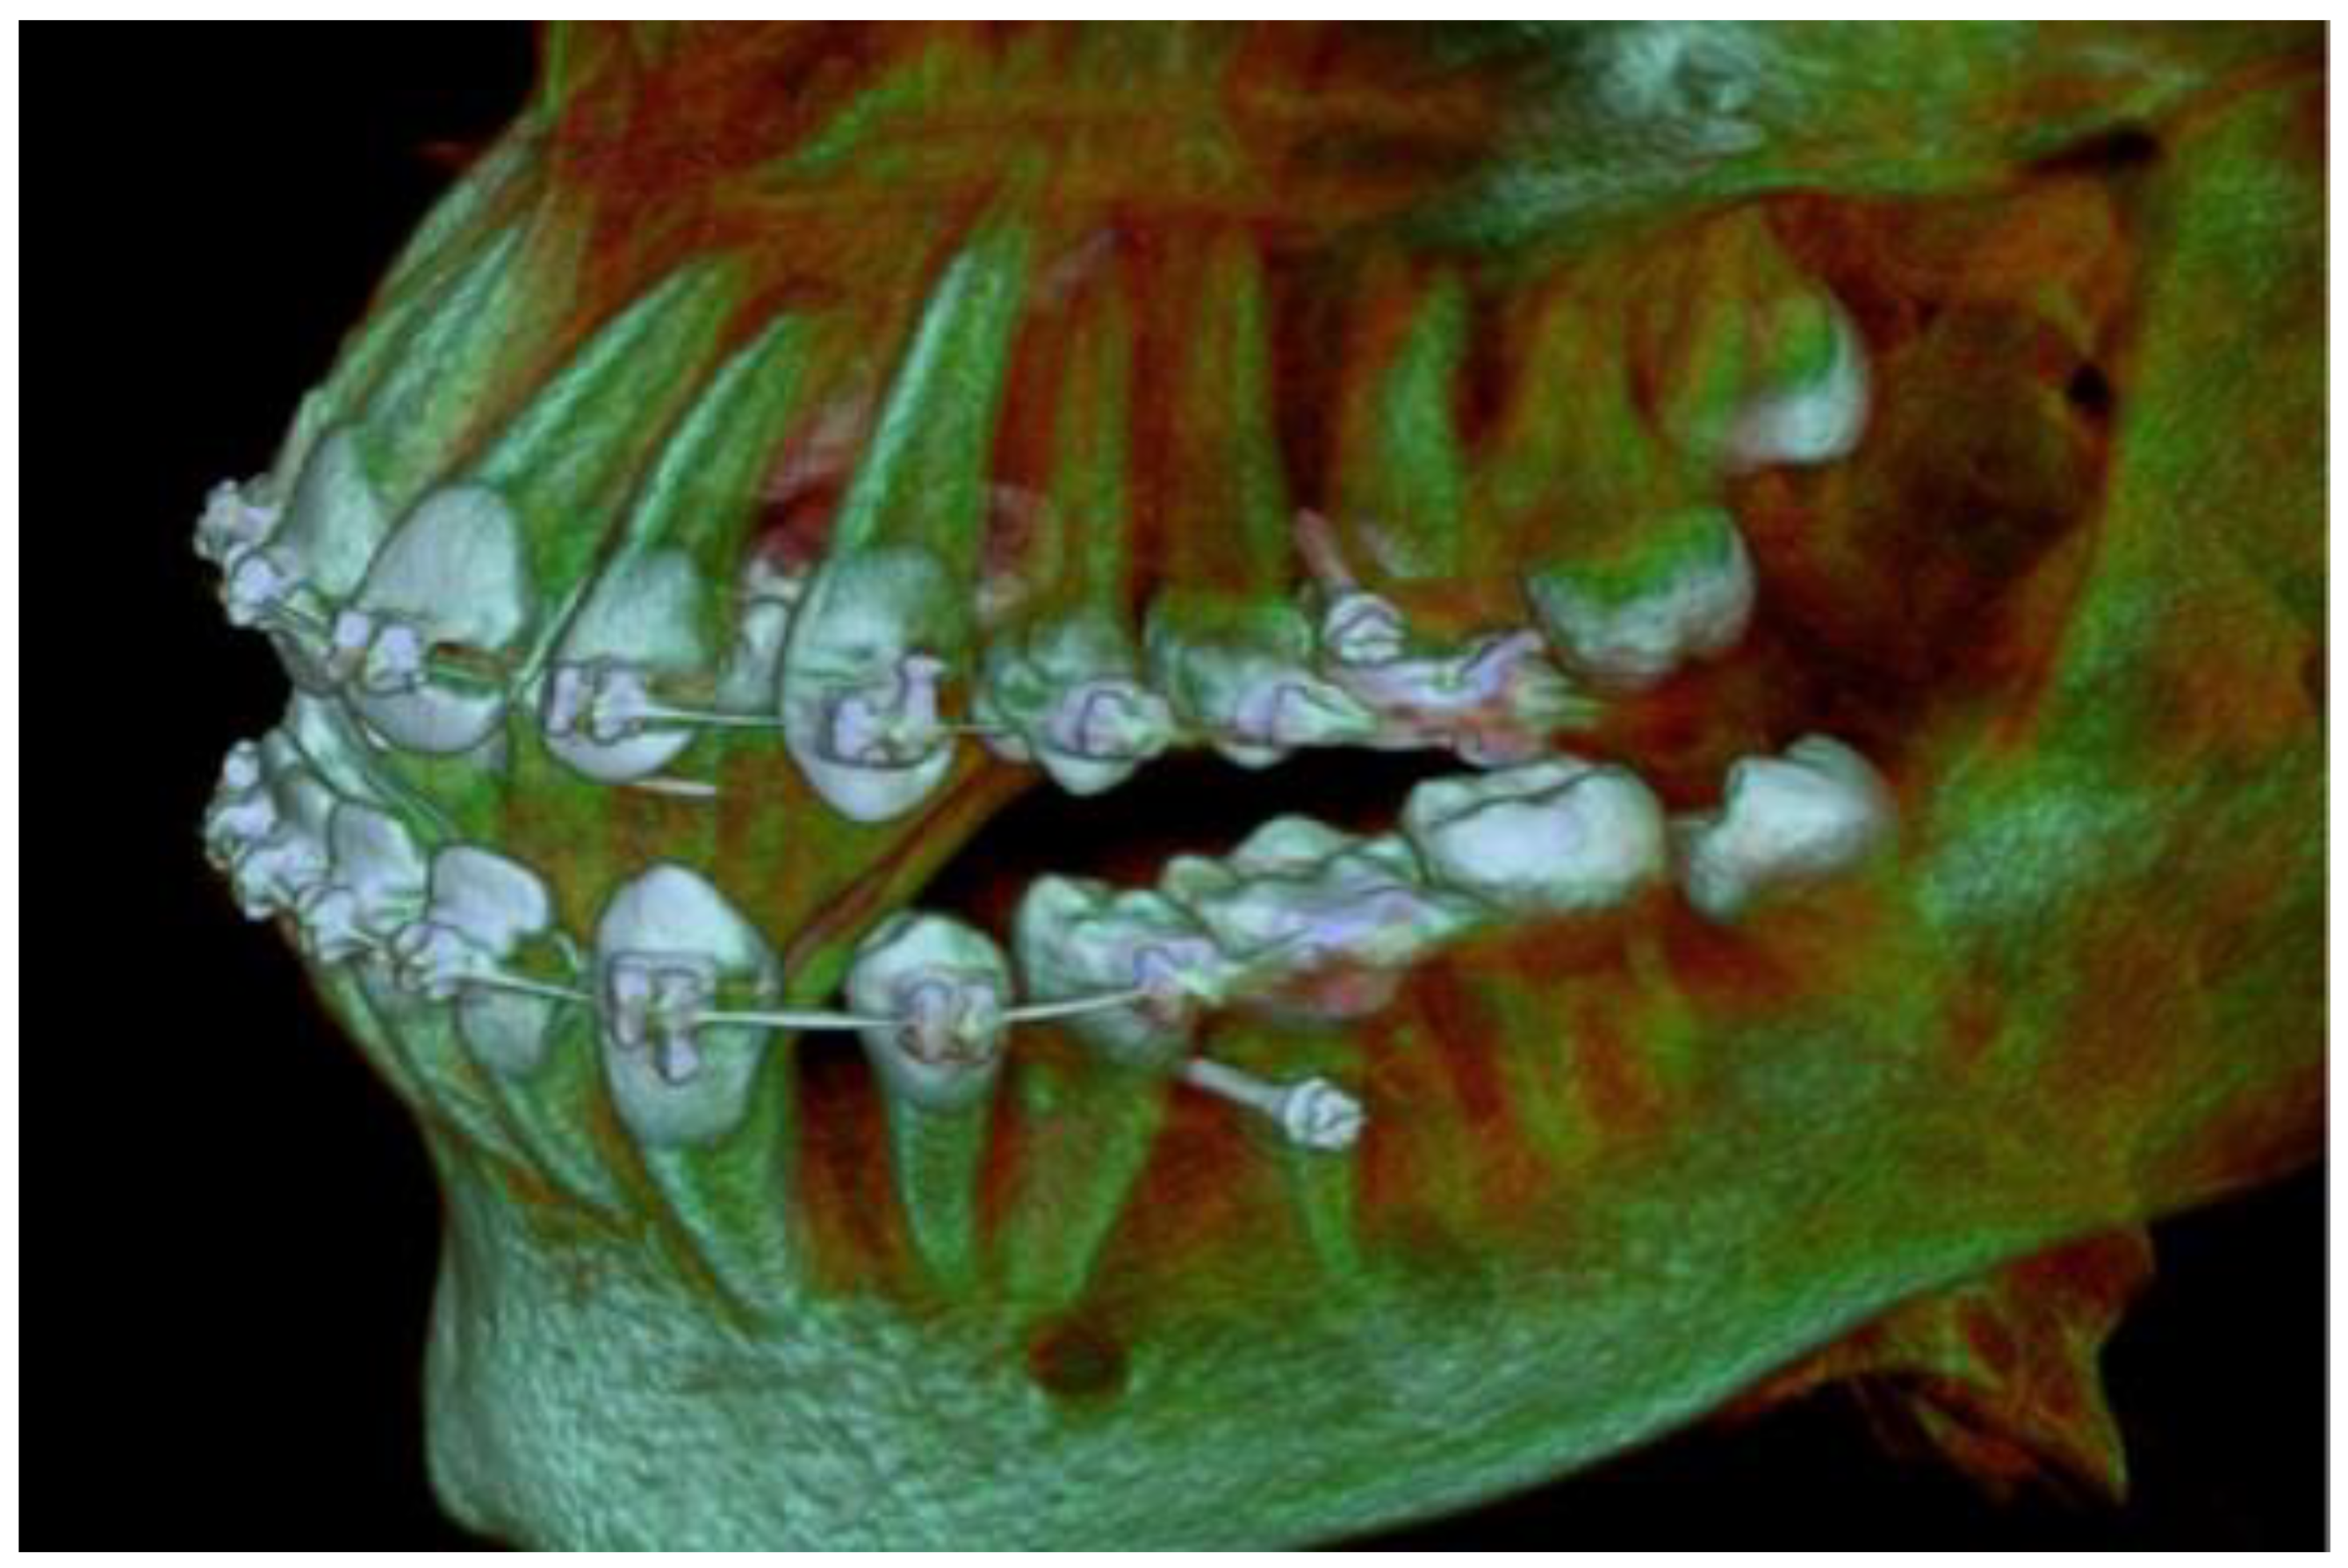

2. Materials and Methods

3. Results